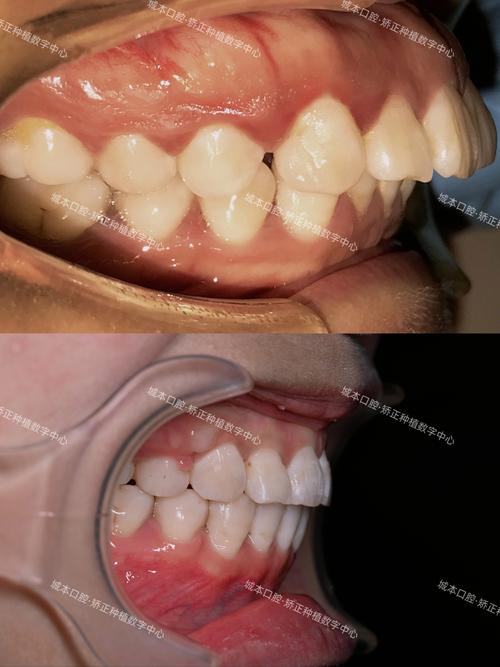

牙齿倾斜的发生速度与缺牙时间、缺牙位置密切相关,缺牙后3-6个月即可观察到邻牙的轻微移位,1-2年后倾斜程度会明显加重,尤其是后牙缺失,因承受的咀嚼力更大,邻牙倾斜的速度和幅度往往比前牙更显著,缺牙导致的牙槽骨吸收也会加速牙齿移位——牙槽骨因失去功能性刺激而萎缩,进一步削弱了对牙齿的支撑力,形成“牙齿倾斜—牙槽骨吸收—牙齿进一步倾斜”的恶性循环。

牙齿正畸通过施加持续、轻柔的生物力,引导倾斜的牙齿移动至正常位置,恢复牙列的整齐与稳定,针对缺牙后牙齿倾斜的情况,正畸治疗的目标主要包括:关闭缺牙间隙(或为种植牙创造空间)、纠正邻牙倾斜、恢复咬合功能、改善面部美观,具体治疗方案需根据患者的缺牙时间、年龄、牙槽骨条件、咬合关系等因素综合制定。

- 方案设计:根据检查结果,确定是否需要关闭缺牙间隙,对于青少年患者,若牙槽骨条件良好,可通过正畸直接关闭间隙,避免未来种植牙的需求;对于成年人,尤其是后牙缺失,通常建议保留缺牙间隙,先通过正畸排齐倾斜的邻牙,为后续种植牙创造良好的骨条件和空间。

| 后牙缺失,缺牙时间长 | 重度倾斜(>30°) | 保留间隙,先排齐邻牙,再行种植修复 | 需评估牙槽骨高度,必要时植骨 |